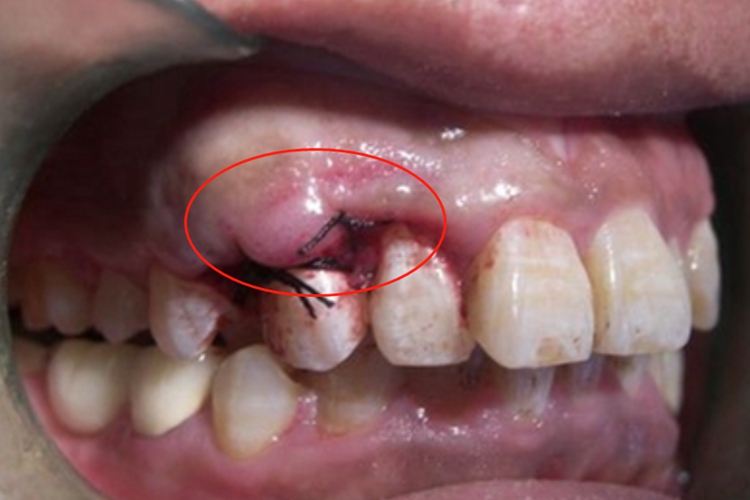

牙龈瘤的肿块较局限,呈圆形或椭圆形,有时呈分叶状,大小不一,直径由几毫米至数厘米。肿块可如息肉状,较大时类似于大包样损害,甚至可以遮盖一部分牙及牙槽突,表面可见牙压痕。

对于牙龈瘤可遵医嘱在局麻下手术切除,切除必须彻底,否则易复发。如果复发,仍可手术切除。多次复发者,即使病变波及的牙无松动,也应就医后将牙拔除,防止再发。